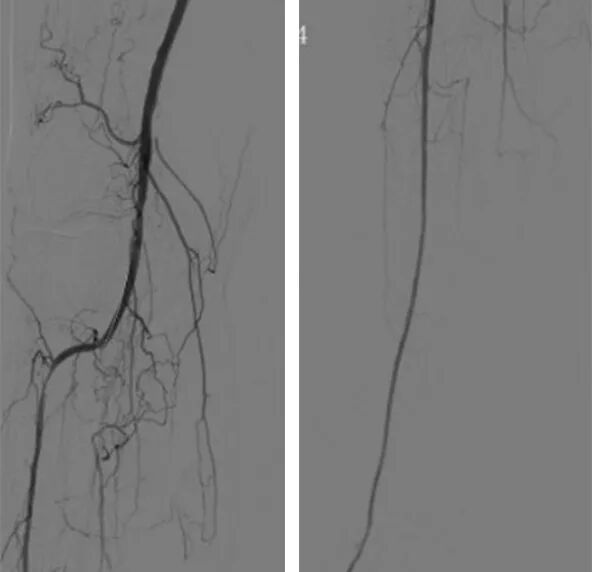

6、术中对于血栓组织予以直视下取栓,股浅动脉近端分叉病变予以内膜剥脱成形,股浅动脉远端病变予以置入Smart裸支架6*150mm、6*100mm,对于股浅动脉瘤予以缩窄缝合并将支架近端超过瘤样病变至少1cm,并予以5*150mm球囊后扩支架。

7、最后造影显示右股腘动脉显影通畅,支架形态良好,膝下胫前动脉显影通畅,未见明显造影剂滞留现象,遂撤出导丝导管,左腹股沟穿刺处予以置入Exoseal封堵器封堵穿刺点后,予以加压包扎。

8、患者术后一周康复出院,出院前复查ABI右侧0.78(较术前0.40明显提升),出院带药:双通道抗凝及抗血小板治疗(阿司匹林肠溶片100mg 联合利伐沙班片10mg )。